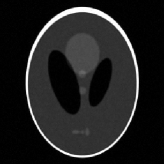

where J1subscript𝐽1J_{1} is the first kind Bessel’s function of order 111. Then using the variable density random sampling method in [46], we generate 20%percent2020\% undersampled k-space data. The complex white Gaussian noise is also added so that the resulting SNR of the samples is approximately 25dB25dB25\mathrm{dB} (See Fig. 3).

Refer to caption

(a) Fully sampled

(b) Ground truth

(c) Sample mask

(d) Undersampled

Figure 3: Dataset for the phantom experiments. Fully sampled k-space data, its inverse DFT as a ground truth, the undersampling mask, and the undersampled k-space data.